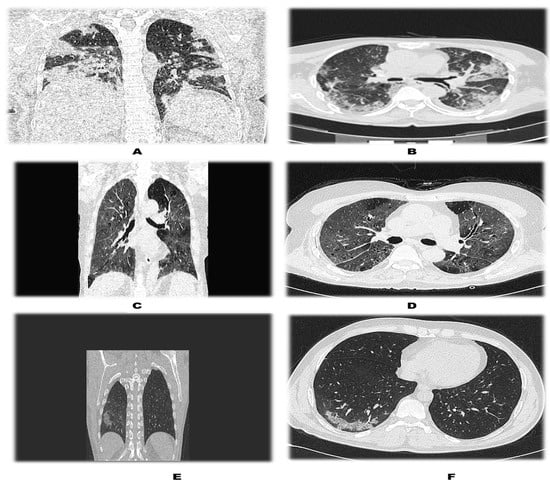

| CLASS | CTSS (out of 25) |

| MILD | 0–11 |

| MODERATE | 12–18 |

| SEVERE | >18 |

| CT Severity Score | Patients without DM (n = 115) | Patients with DM (n = 37) | Total | p Value |

|---|---|---|---|---|

| 0–11 {Mild} | 65 (56.52%) | 12 (32.43%) | 77 (50.66%) | 0.024 |

| 12–18 {Moderate} | 46 (40%) | 22 (59.46%) | 68 (44.74%) | |

| >18 {Severe} | 4 (3.48%) | 3 (8.11%) | 7 (4.61%) | |

| Total | 115 (100%) | 37 (100%) | 152 (100%) |